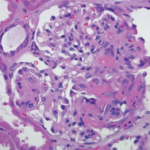

Based on the classification system developed by the Chapel Hill Consensus Conference, anti-neutrophil cytoplasmic antibody (ANCA) associated vasculitis is defined as a necrotizing vasculitis involving small vessels that is associated with myeloperoxidase (MPO) ANCA or proteinase 3 (PR3) ANCA and displays minimal immune deposits. The mechanism behind the pathogenesis of ANCA-associated vasculitis is not fully…

SAN DIEGO—At the 2017 ACR/ARHP Annual Meeting this past November, three researchers discussed the latest ANCA-associated vasculitis (AAV) research, including studies on AAV pathogenesis, therapies and remission maintenance. In the Philip Hench, MD, Memorial Lecture, J. Charles Jennette, MD, chair in pathology and laboratory medicine at the University of Carolina at Chapel Hill in Chapel…